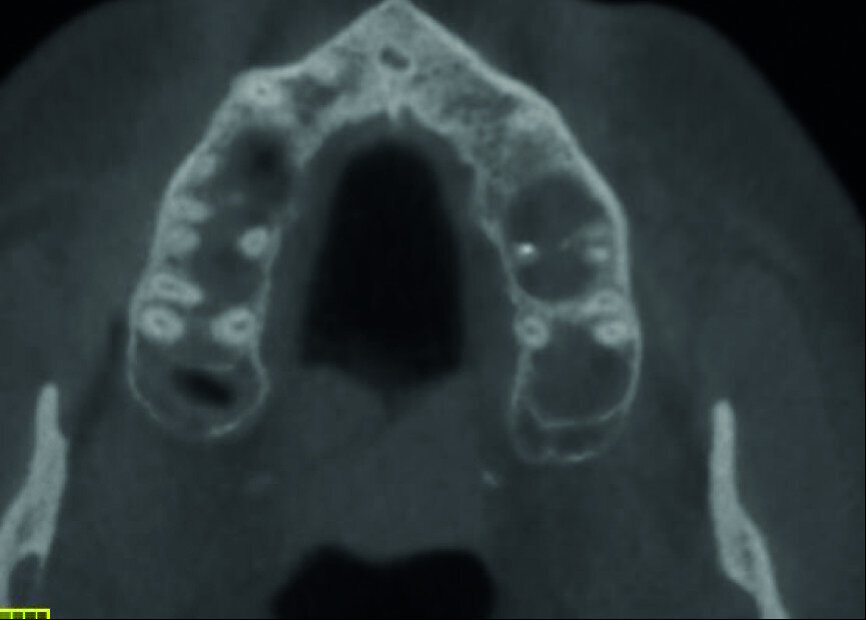

A patient was referred to the office with problems related to separated files. He was a pilot and was complaining of pus draining from his nose when flying. From the preoperative radiograph (Fig. 1), it was clear that there were two separated file fragments in the mesial canals and one cone passing beyond the apex in the palatal root. I requested an iCAT scan, and from this, the left sinus was clearly almost full with inflammatory fluid (Fig. 2) and the cone in the palatal canal was clearly emerging into the sinus. We could also see the two separated files in the two mesial canals clearly in the MPR view (Figs. 3 & 4), as well as another file entering the sinus and not attached to the canal (Fig. 5). We could see the file using different filters (Figs. 6–9), as well as the inflammation inside the sinus and the separated file. We additionally gained a better idea of the location of the cone protruding from the palatal canal into the sinus.